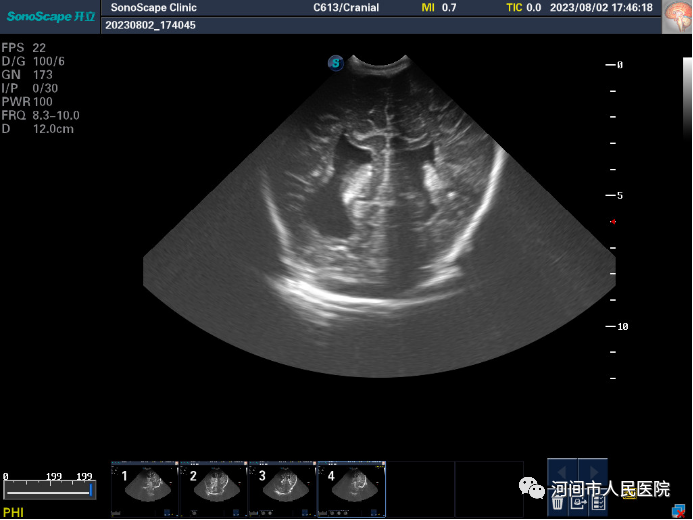

▲新生兒(er) 腦室內(nei) 出血